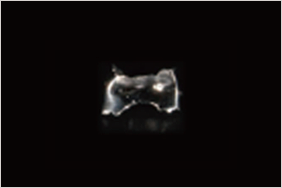

虫歯になった歯や、歯冠部を失ってしまった歯の根部を補強するものです。神経を失った歯はもろくなっているため、歯の根部にコアと呼ばれる土台を入れ、補強した上でかぶせものをします。

歯を削って土台(コア)をたてて被せ物をセットしました。

土台(コア)5,000円、被せ物セラミック90,000円

セラミックが透過性があるため光が当たると黒く見える